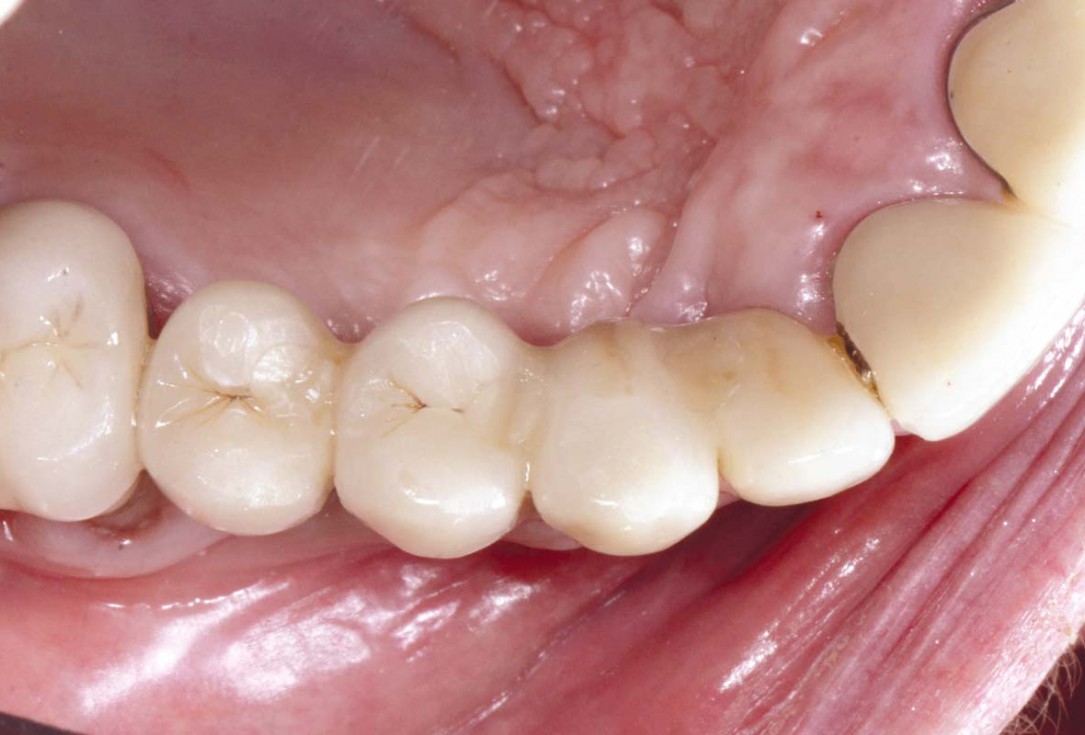

Initial clinical situation: Bone defect in the upper right maxilla (teeth #14-16)